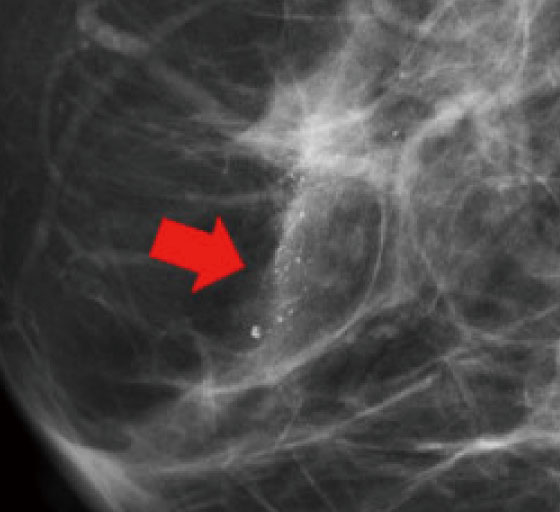

マンモグラフィ検査は、乳房を挟み圧迫しながら撮影を行う検査です。乳房を薄く広げることによって、乳房内をより鮮明に見ることができ、触ってもわからないような早期の小さながんや、非常に細かい石灰化をみつけることができます。圧迫により痛みを伴いますが、患者さんの様子を観ながら行いますので、安心して検査をお受けください。撮影はすべて女性技師で対応しています。

マンモグラフィでは、乳房内の腫瘤(図1)、石灰化(乳腺内にできるカルシウムの粒で、悪性、良性の場合があります)(図2)、構築の乱れ(病変による正常乳腺の構造のゆがみ)などが客観的に描出されます。

図1.腫瘤

図2.石灰化